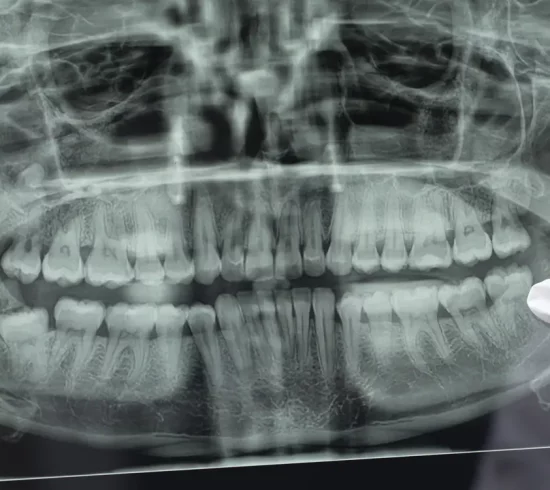

La ortopantomografía o radiografía panorámica es una técnica radiológica que representa una imagen general de los maxilares, la mandíbula y los dientes, por tanto, es de primordial utilidad en el área dentomaxilomandibular.

Su papel en el diagnóstico odontológico, no solo de los dientes sino también del maxilar y mandíbula, es fundamental. Prácticamente es utilizada de forma sistemática en odontología, llegando a ser un arma diagnóstica rutinaria. El valor diagnóstico de la ortopantomografía en cirugía bucal, implantología, ortodoncia, periodoncia, patología oral y dental está claramente demostrado.

La ventaja fundamental que nos permite esta técnica es la visualización completa en una sola imagen de todo el área maxilar, superior e inferior, así como sus anexos (mesoencía, ligamentos, articulaciones, etc). Eso nos permite descubrir patologías que escapan a la exploración rutinaria y que sólo podmeos ver a través de esta técnica, pudiendo prevenir de mejor manera cualquier problema.